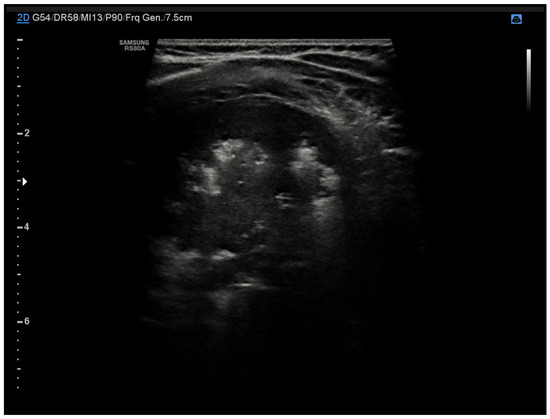

4.3. Lung Abscess